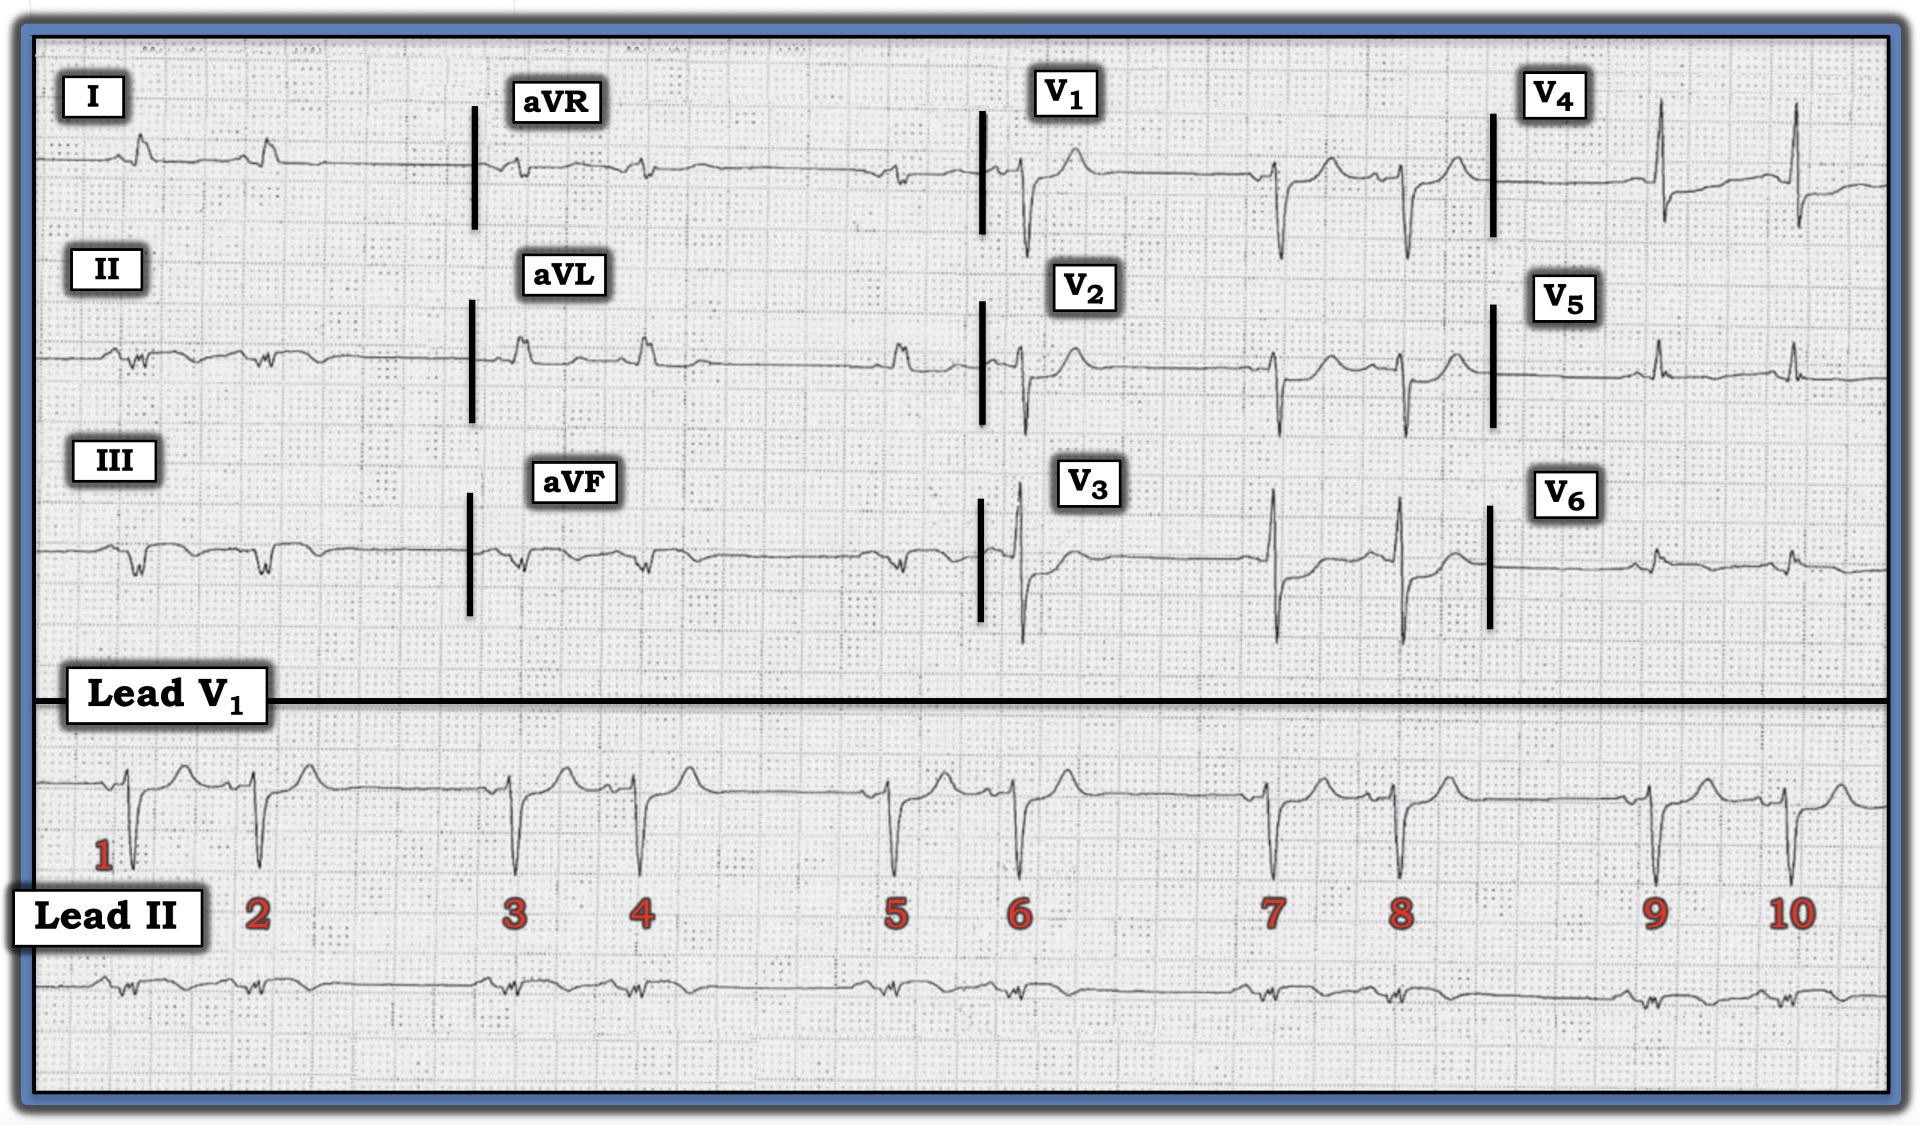

The medical providers in this case were concerned the cause of the bigeminal rhythm in the figure below was sinoatrial (SA) block. Do you agree? Are there other things to be concerned about?

Interpretation: The rhythm in this tracing fits the definition of “bigeminy” because there are repetitive groups of two beats, here with similar longer-followed-by-shorter R-R intervals.

• The underlying rhythm is sinus, as determined by the presence of an upright P wave with a constant PR interval in the long lead II rhythm strip.

• The most common cause of a bigeminal rhythm such as that shown in the figure is atrial bigeminy, in which every other beat is a premature atrial contraction (PAC).

• That said, two features in this rhythm are different than the usual case of atrial bigeminy. These two features are: i) the fact the R-R interval between the two beats in each group is precisely half the longer R-R interval between groups and ii) the similarity in P wave morphology of virtually all P waves in almost all 12 leads.

Atrial bigeminy typically results in a “reset” of the SA node, such that the longer R-R intervals usually will not be precisely twice the shorter R-R intervals. Because PACs by definition arise from an ectopic site within the atria, P wave morphology of PACs usually is readily recognized as different than the P wave morphology of sinus beats.

• In contrast, type 2 SA block with 2:1 AV conduction is characterized by a uniform P wave morphology, since all impulses arise from the SA node, and a precise doubling of longer R-R intervals compared to the shorter R-R intervals.

• That said, atrial bigeminy, in which the ectopic atrial focus arises from an atrial site close to the SA node, may manifest similar P wave morphology in most, but not all, 12 leads. Given how much more common atrial bigeminy is — and given subtle-but-real differences in P wave morphology in leads II, III, and aVF — it is most likely the rhythm in this tracing is the much more common atrial bigeminy.

NOTE: Determining the rhythm in this case is not the most important ECG finding. It turns out this patient presented with new chest pain — and the fragmented inferior lead Q waves with subtle, coved ST elevation and T wave inversion — in association with reciprocal changes in lead aVL, as well as maximal ST depression in leads V1 through V3 — suggested acute infero-postero infarction in progress.